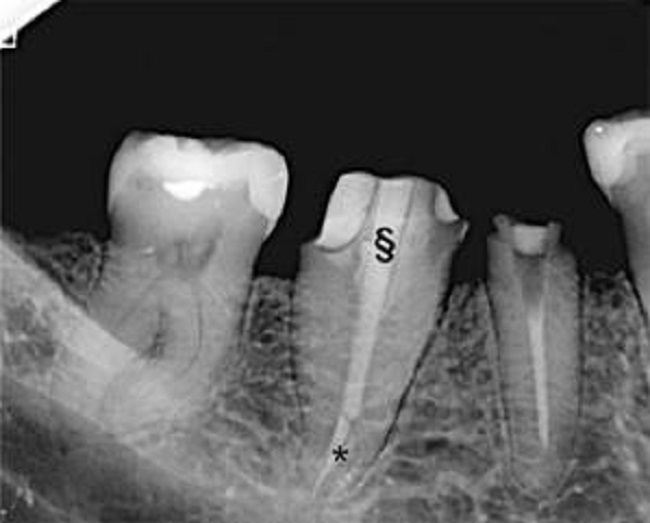

El CBCT (Vatech Pax Zenith CBCT machine, 120 kVp and 9.0 mA, FOV 8 × 6 cm, voxel size 0.12 mm) fue visualizado utilizando el software GALILEOS Viewer 1.9 (SICAT GmbH & Co. KG, Bonn, Germany), obteniendo una imagen tridimensional del diente para su evaluación en secciones axiales, sagitales y coronales. Las imágenes confirmaron la presencia de una sola raíz con un único canal de forma ovalada, extendido desde la cámara pulpar al ápice, correspondiendo al mencionado tipo I de Vertucci (Figura 2).

Confirmadas así las características inusuales estimadas originalmente y estableciéndose la no existencia de condiciones desfavorables para continuar el procedimiento, la paciente fue citada para una segunda sesión para finalizar el tratamiento endodóntico. Esta se concretó siete días después, momento en el que fue retirada la obturación provisoria y se continuó la preparación quimiomecánica ya iniciada en la primera sesión. El tratamiento se finalizó mediante obturación con técnica de compactación lateral de gutapercha en frío para lograr un mejor control apical y sellado del canal siguiendo los protocolos estándar para ese tipo de anatomía canalicular. Se realizaron los controles apropiados a los 7 y 14 días corroborando la ausencia de signos y síntomas clínicos y radiográficos remitiéndose nuevamente el caso a su odontólogo tratante para continuar con la rehabilitación protésica ya planificada (Figura 3).